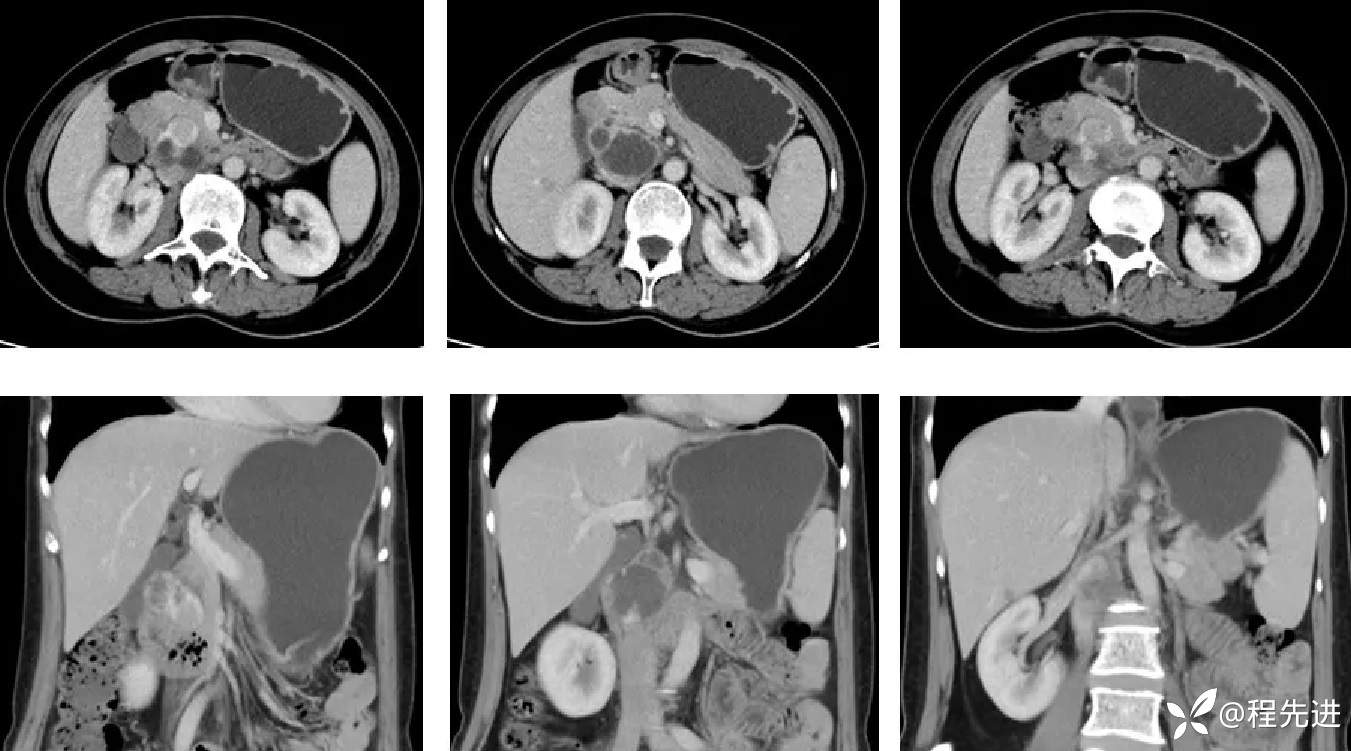

CT动脉期:

CT静脉期: